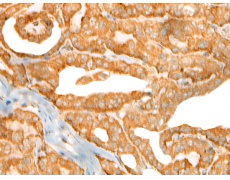

IHC positive control: |

Human thyroid cancer and Human prostate cancer |

IHC Recommend dilution: |

30-150 |